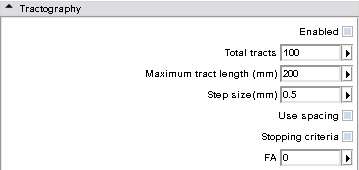

- Tractography panel: